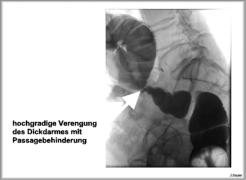

Ein Darmverschluss kann durch viele Ursachen bedingt sein. Möglich sind Tumore im Darm

(Darmkrebs), die die Passage im Darm verhindern. Es können auch Tumore außerhalb des

Darms oder auch Verwachsungen, die den Darm von außen einengen und dadurch einen

Verschluss hervorrufen, vorliegen. Entzündungen oder Durchblutungsstörungen im Bauchraum

können ebenfalls einen Darmverschluss bedingen.